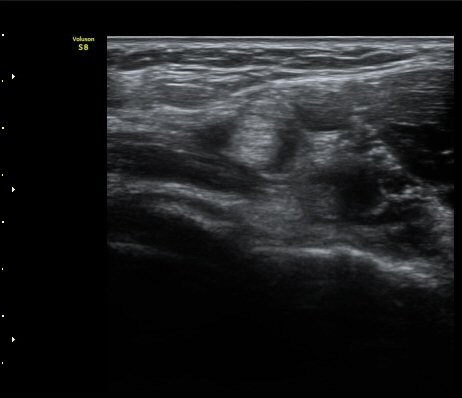

ÆÈ²ÞÄ¡ ¾Õ Ⱦ´Ü¸é°Ë»ç¿¡¼­ À̵ιڱÙÀÌ ÈûÁÙ·Î ÀÌÇàµÇ´Â °ÍÀÌ °üÂûµÈ´Ù(±×¸² 1, 2).

ŽÃËÀÚ¸¦ Á¶±Ý ¸»´ÜÀ¸·Î À̵¿ÇÏ´Ï À̵ιڱ٠ÈûÁÙÀÌ ¶Ñ·ÈÇÏ°Ô °üÂûµÇ°í ÇÔÁÙ ÁÖÀ§¿¡